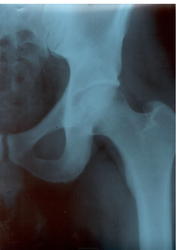

1. Деформирующие коксартрозы Iст. по Косинской здесь можно ставить с двух сторон.  IIст. по каким-то зарубежным неразумным классификациям может быть. Видимые части крестцово-подвздошных суставов без особенностей.

2. Клинические проявления скорей всего связаны именно с АРС-синдромом. А при деформирующих коксартрозах боли в паху нехарактерны.. И для лечения стоит обратиться к врачу работающему со спортивной травмой.

Коксартроз 2 ст. с 2-х сторон.Налицо неравномерное сужение суставных щелей, субхондральный  склероз по верхне-наружным краям вертлужных впалин.

Однозначно - 1 ст с обеих сторон, справа щель уже чем слева, не нужно гипердиагностики - людям жить еще...))) молодой человек и так уж весь разволновался))) и оперироваться бросаться не стоит, это "палка о двух концах", снять обострение, режим и "грани разумного" в физкультуре и др.

я б вообще норму поставила, не так уж и выражено там склерозирование крыш, и некоторая асимметричность ширины р-суставный щелей вполне допустима.

Снимки «не ах», но неравномерное снижение рентгеновской суставной щели отчётливо. Да и кисточки, если приглядеться, видны.